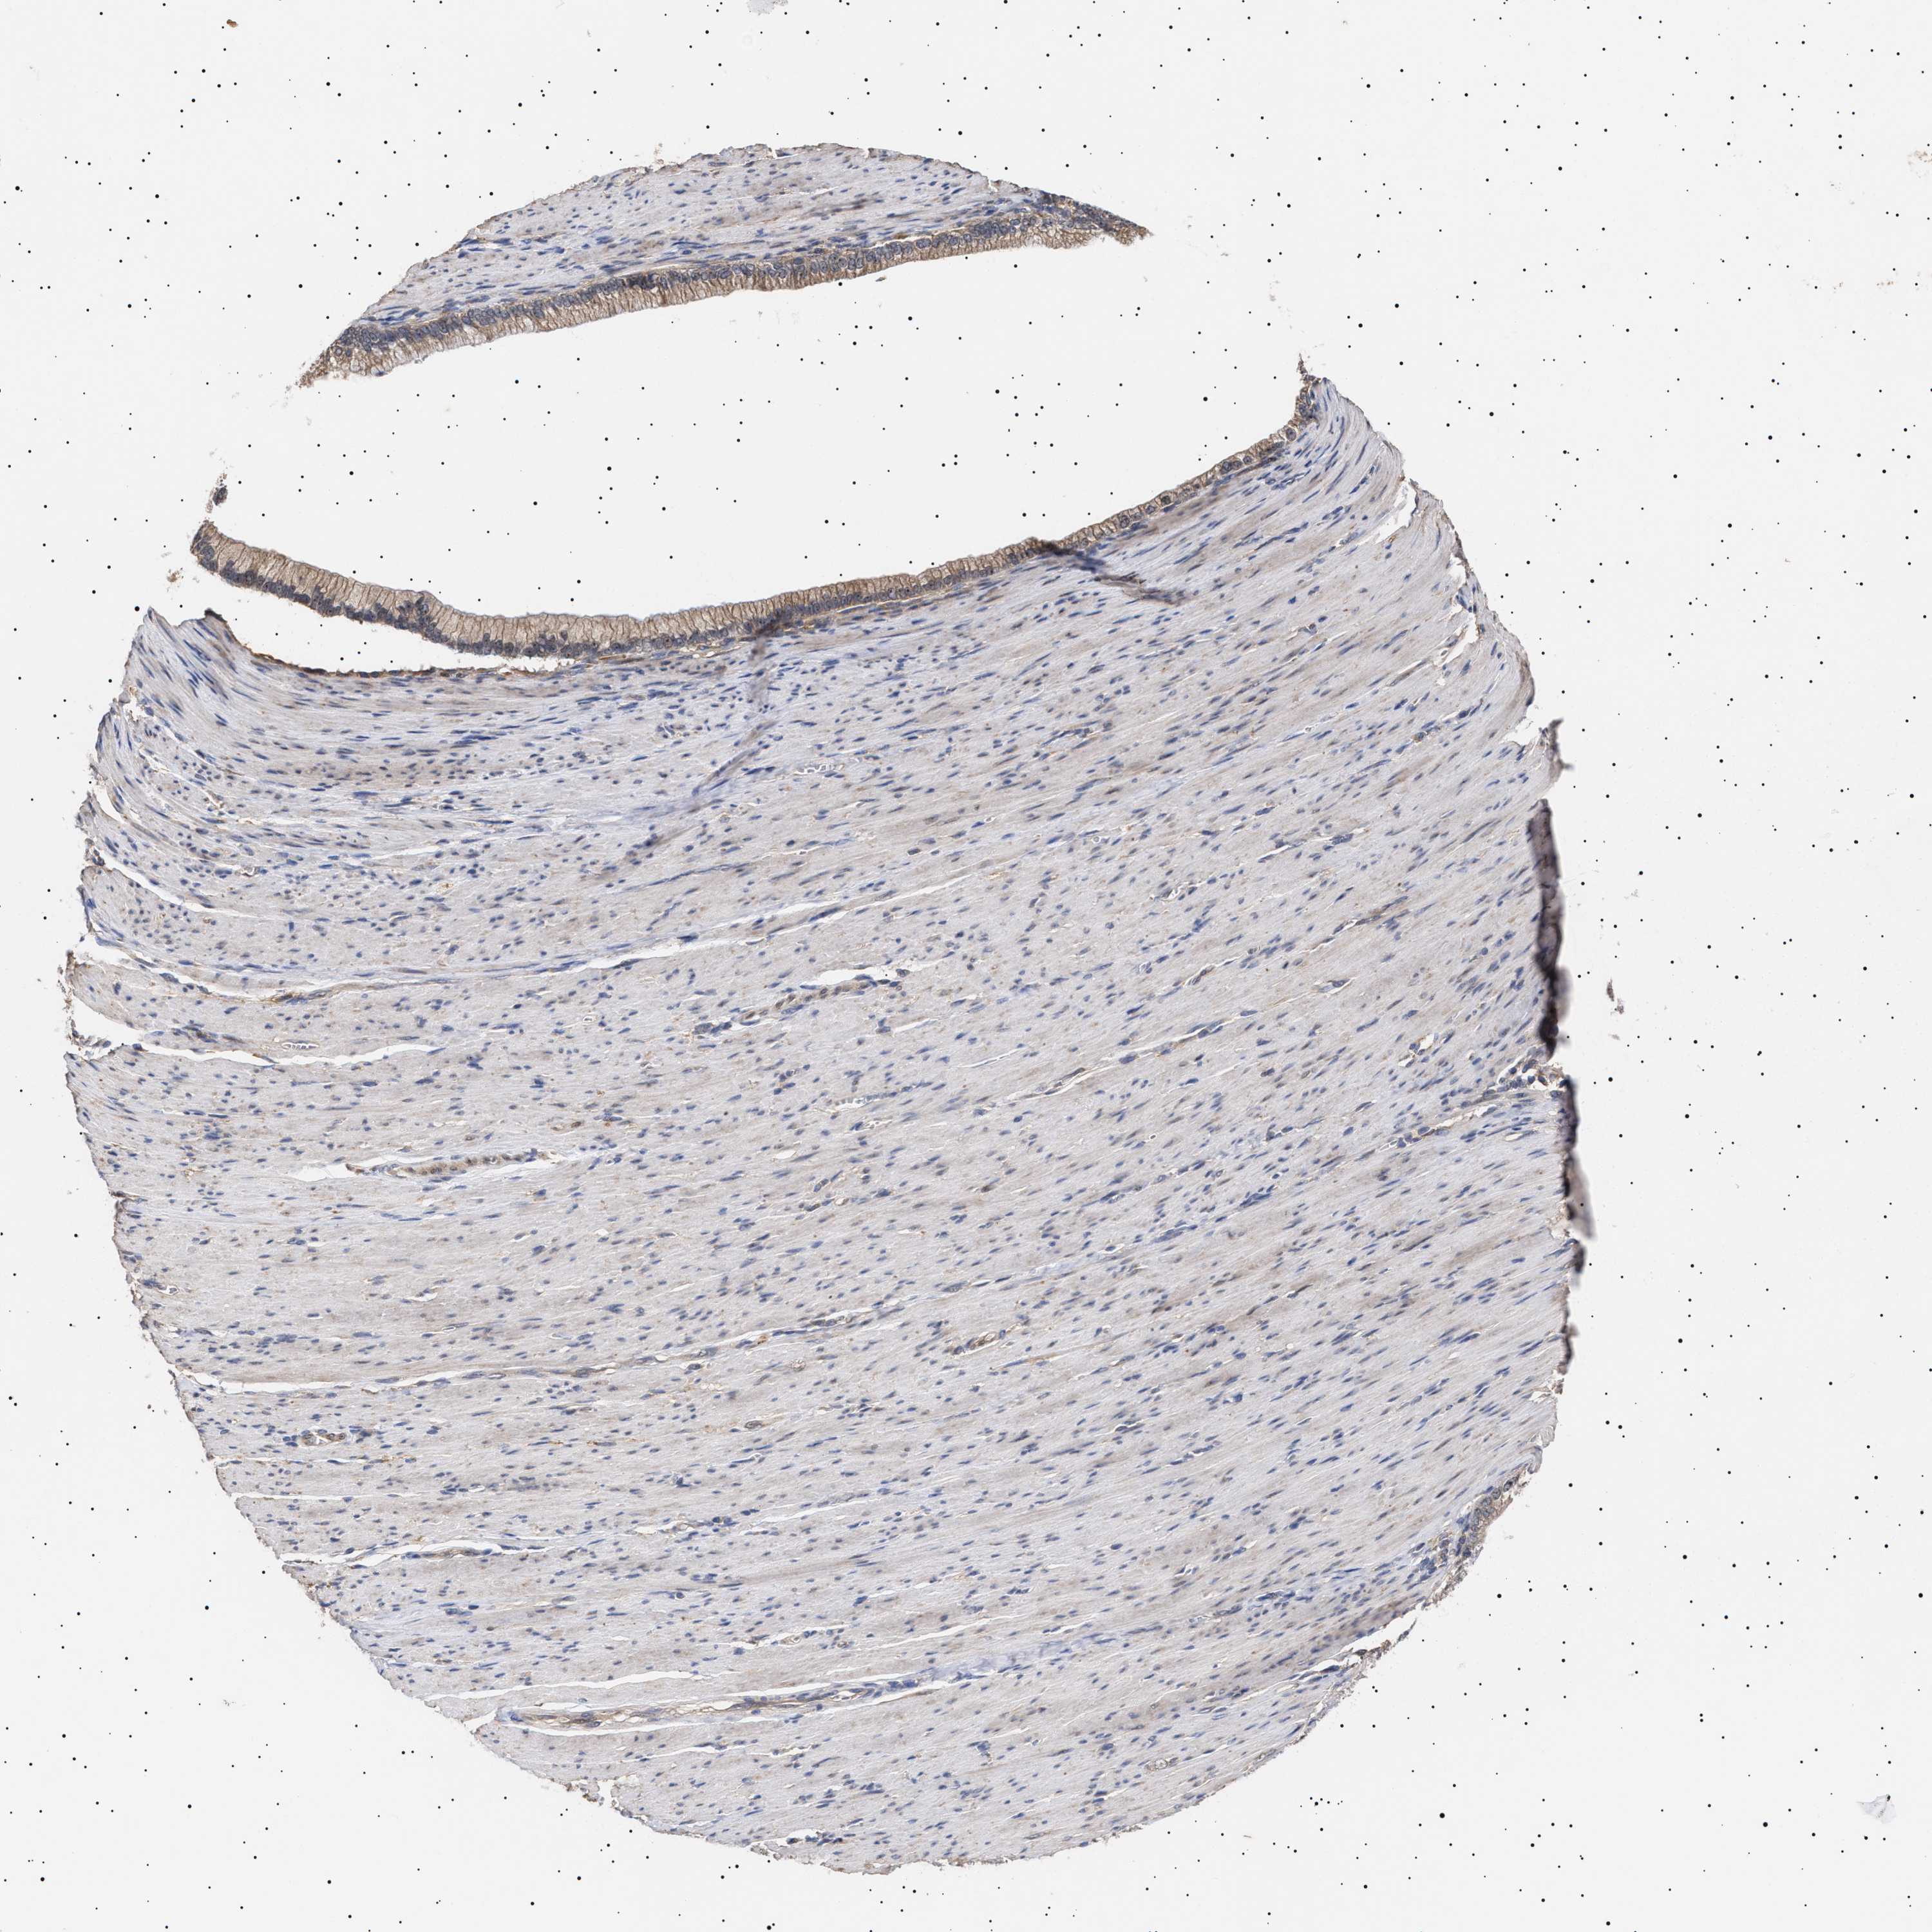

PANCREATIC CANCER - Protein expressioni

A mouse-over function shows sample information and annotation data. Click on an image to view it in a full screen mode. Samples can be filtered based on level of antibody staining by selecting one or several of the following categories: high, medium, low and not detected. The assay and annotation is described here.

Note that samples used for immunohistochemistry by the Human Protein Atlas do not correspond to samples in the TCGA dataset.

Antibody stainingi

Antibody staining in the annotated cell types in the current human tissue is reported as not detected, low, medium, or high, based on conventional immunohistochemistry profiling in selected tissues. This score is based on the combination of the staining intensity and fraction of stained cells.

Each image is clickable and will lead to virtual microscopy that enables deeper exploration of all samples and also displays staining intensity scores, fraction scores and subcellular localization as well as patient and tissue information for each sample.

Antibody HPA021237

Antibody HPA050448

Adenocarcinoma, NOS